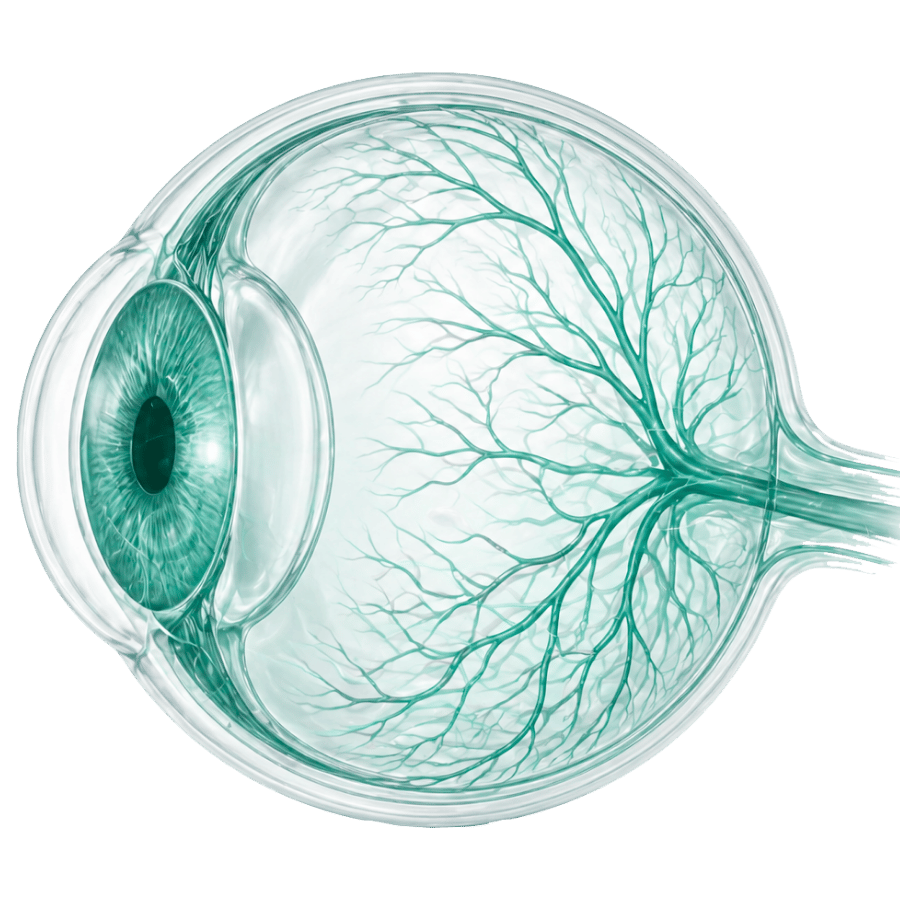

Офтальмология

қызметтер: 33